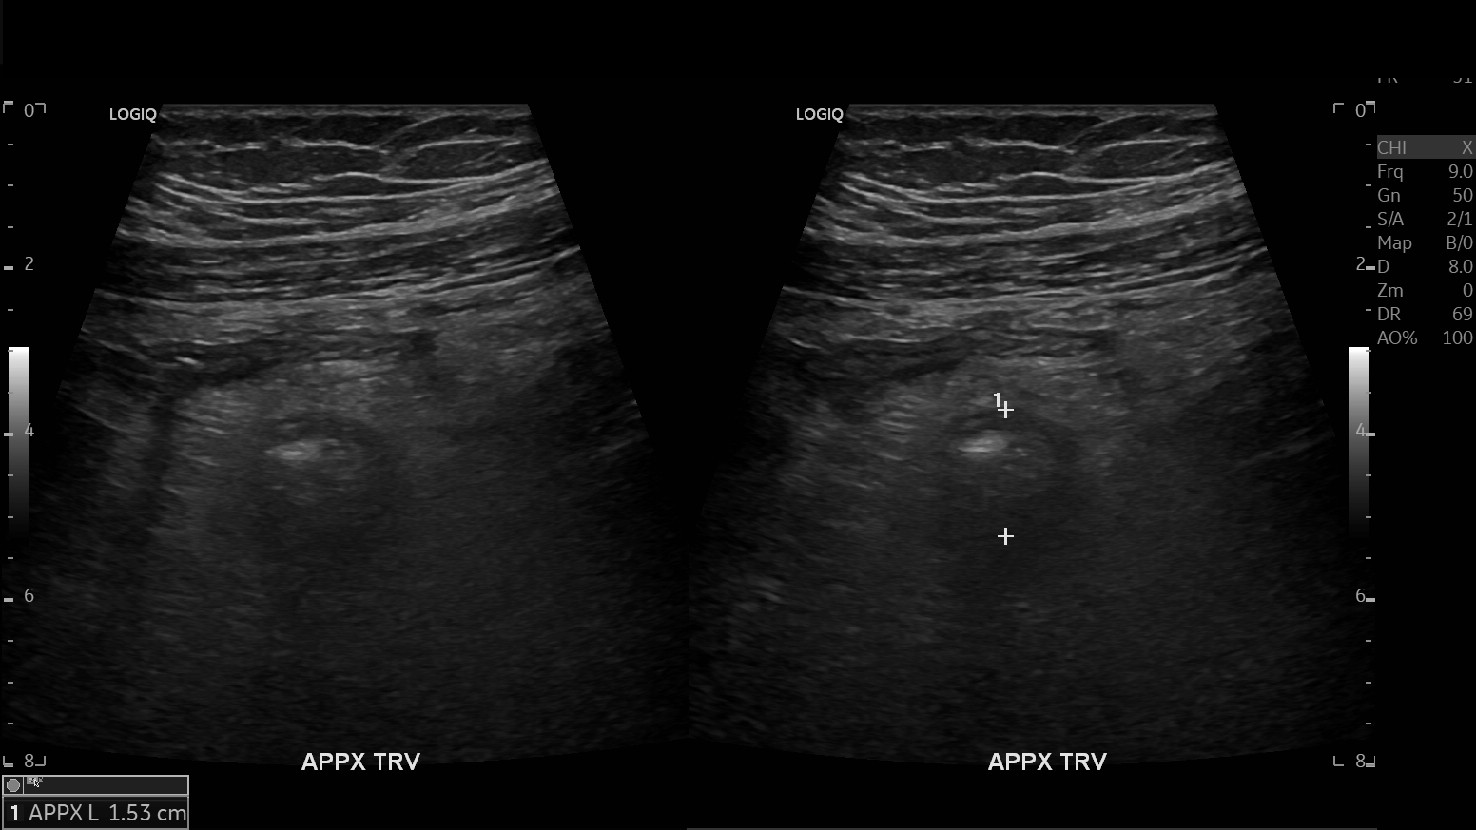

Appendicitis 13

Acute appendicitis @ 1 cm with L2-9mhz and L6-24mhz transducer GE Logiq e10.